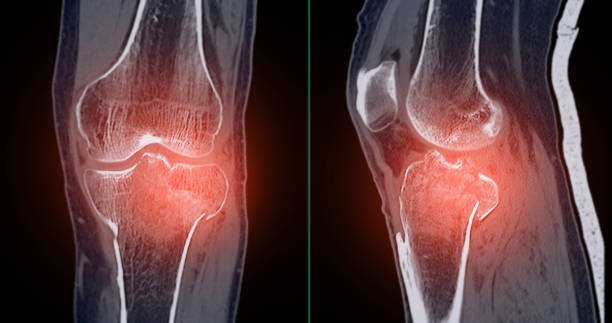

Arthritis

Arthritis rehabilitation reduces pain, improves joint mobility, strength, flexibility, and daily function through guided physiotherapy.

Osteoarthritis

Osteoarthritis rehabilitation reduces joint pain, improves mobility, strength, flexibility, function, and long-term movement confidence safely.